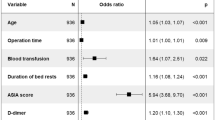

Distinguishing degree

The nomogram predictive model had good discrimination because the ROC curve showed that the nomogram had an AUC value of 0.865 (95% CI 0.780–0.935) in Fig. 7. Further, all 513 patients in this study had Caprini scores ≥ 5 (Fig. 1), which should be defined as patients at high risk of DVT. The AUC of the Caprini score was 0.571 (95% CI 0.479–0.623), which was significantly lower than the 0.865 of the nomogram model (Fig. 7). In terms of patients with femoral fracture, it followed that the discrimination of the nomogram model was better than the Caprini score.